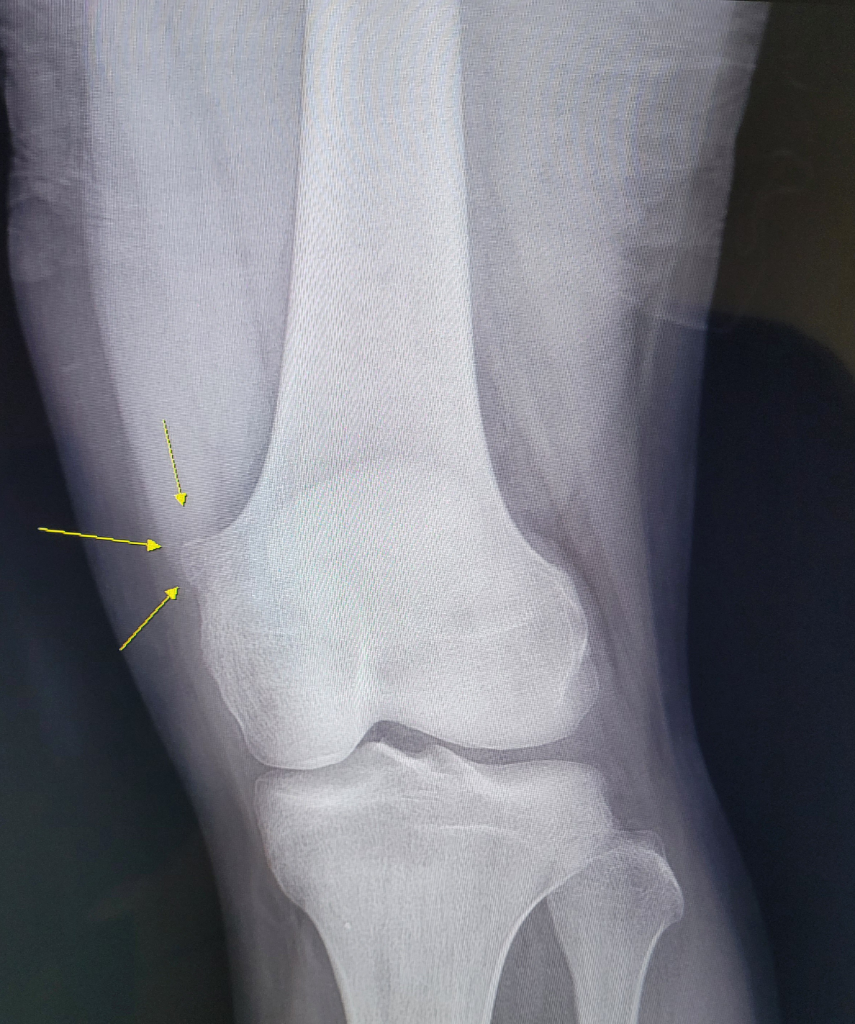

오늘 의원급 정형외과에서 어쩌다보니 무릎 x-ray를 찍게 됐습니다. 그래서 뼈가 저런걸 확인했습니다. 여태 살면서 무릎 x-ray를 찍어본적이 없어서 확인할 기회가 없었어서 저런건지는 모르고 어릴때부터 만지기만 했었습니다. 3개월정도 전에 뼈 모양이 다른걸로 걱정하느라 정형외과 가서 초음파를 했었는데 초음파상으로는 그냥 뼈가 튀어나온걸로 확인하고 넘어갔었습니다. 이번에 이 사진을 보시고는 원장님이 별거 아닌걸로 보인다고 하셨지만 맘편해지려면 근처 상급병원가서 검사를 해보라고 하셔서 바로 다녀왔고 거기서도 신경쓸 필요가 없는 양상이라고 하셨습니다.

모양 및 위치상 악성종양 등의 가능성은 매우 떨어져 보입니다.

전혀 걱정하실 필요는 없지만, 만약 관찰도중 크기가 커지거나 변화가 있다면 그때는 다시 병원에 내원하시어 다시 검진을 받으시는 것을 추천드립니다.